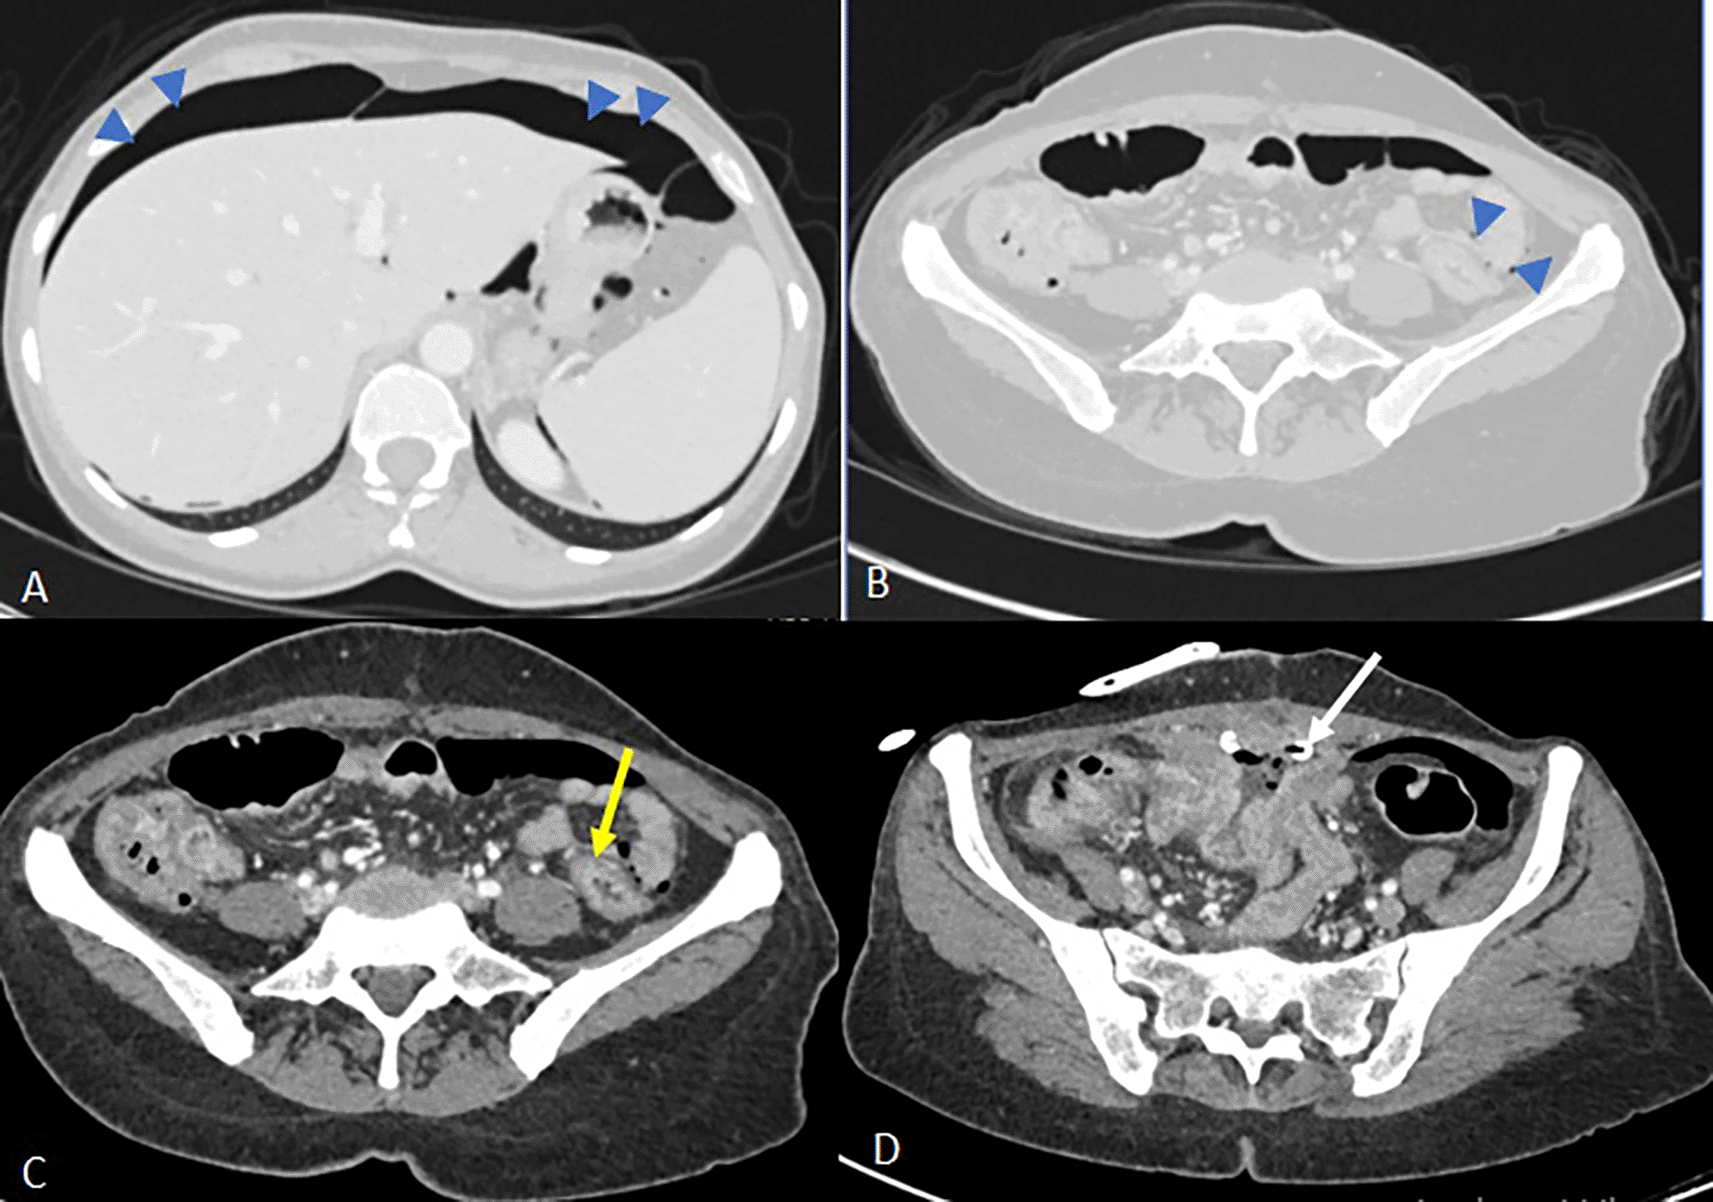

Emergency CT imaging revealed pneumoperitoneum, circumferential rectosigmoid wall thickening with submucosal edema, suspected parietal defect (6 cm), increased supravesical collection size, and new peritoneal fluid (Figure 6).

Image C shows a regular circumferential thickening of the rectosigmoid junction (yellow arrow) silhouetted by extra-digestive air bubbles without any formally identifiable parietal defect.

In image D, there is a partial regression of the supravesical collection with the drainage catheter in place (white arrow). However, there is persistent regular thickening of the ileal loops where the fistulous tracts are located and reactive infiltration of the surrounding fat, with no detectable intra-luminal foreign body in the digestive tract.